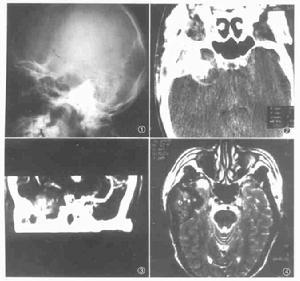

CT 和 CTA圖像

CT圖像 表現主要有骨質異常,硬膜竇異常擴大及腦血管的異常,如顱骨內板血管壓跡明顯,大靜脈竇的異常擴張。病情發展嚴重時甚至可見廣泛的腦皮層靜脈迂曲擴張,呈蚯蚓狀。

M RI(核磁共振成像 )和 M RA

其影像學顯示類似於 CT 、 CTA ,但其解析度較 CT 、 CT A 高,可以提供患者蛛網膜下腔及腦實質的情況,能較清楚地顯示瘺口、增粗的供血動脈,迂曲擴張的引流靜脈及靜脈竇的情況,MRI顯示瘺口緊鄰硬膜竇,並有“流空”現象,可提示本病。

頭顱X線 2. 體位檢查:有無顱內雜音、突眼、視力減退、腦膜刺激征及頭皮靜脈曲張等。 3. 頸 顱超聲檢查(TCD): 雙側頸內動脈及椎動脈常規檢查,病變動脈有血流速度加快,搏動指數減弱或消失。

4. 頭顱 X線檢查:有些患者可由於血管長期充血引起血管溝加深、變粗和骨質增生現象。

5. CT掃描和MRI(MRA):應做平掃加增強,常不能發現病變本身,但可發現靜脈竇血栓形成,血管擴張或出血和腦積水。